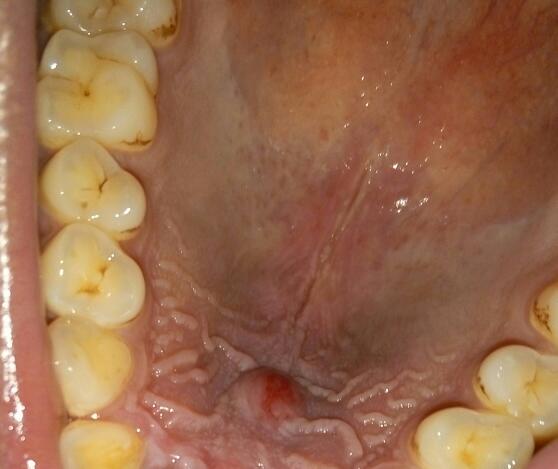

口腔上颚疼痛起泡,总感觉里面好像有水一样舌头顶着会动感觉痛到神经

这是什么情况,口腔壁长泡能自愈吗